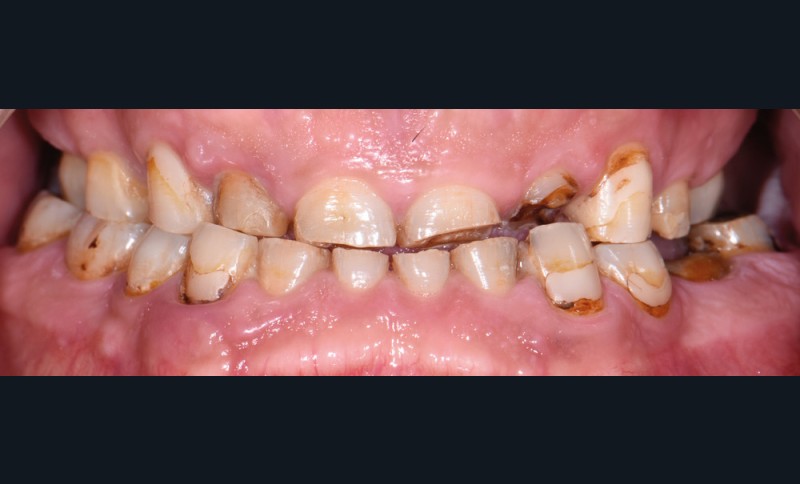

Au vu du contexte para-fonctionnel et de l’étendue de la perte tissulaire, des coiffes périphériques minimalement invasives ont été choisies afin de restaurer l’esthétique et la fonction. Actuellement, aucun consensus n’est fait sur le choix du matériau d’infrastructure à privilégier. Les matériaux hybrides usinables présentent des propriétés mécaniques, physiques et biologiques intéressantes en contexte d’usure sévère (e.g., module d’élasticité, résistance à la propagation de fêlures, facilité de réintervention). Une réhabilitation globale avec remontée de dimension verticale d’occlusion (DVO) par l’intermédiaire de coiffes composites renforcés en nano-céramiques est décrite.